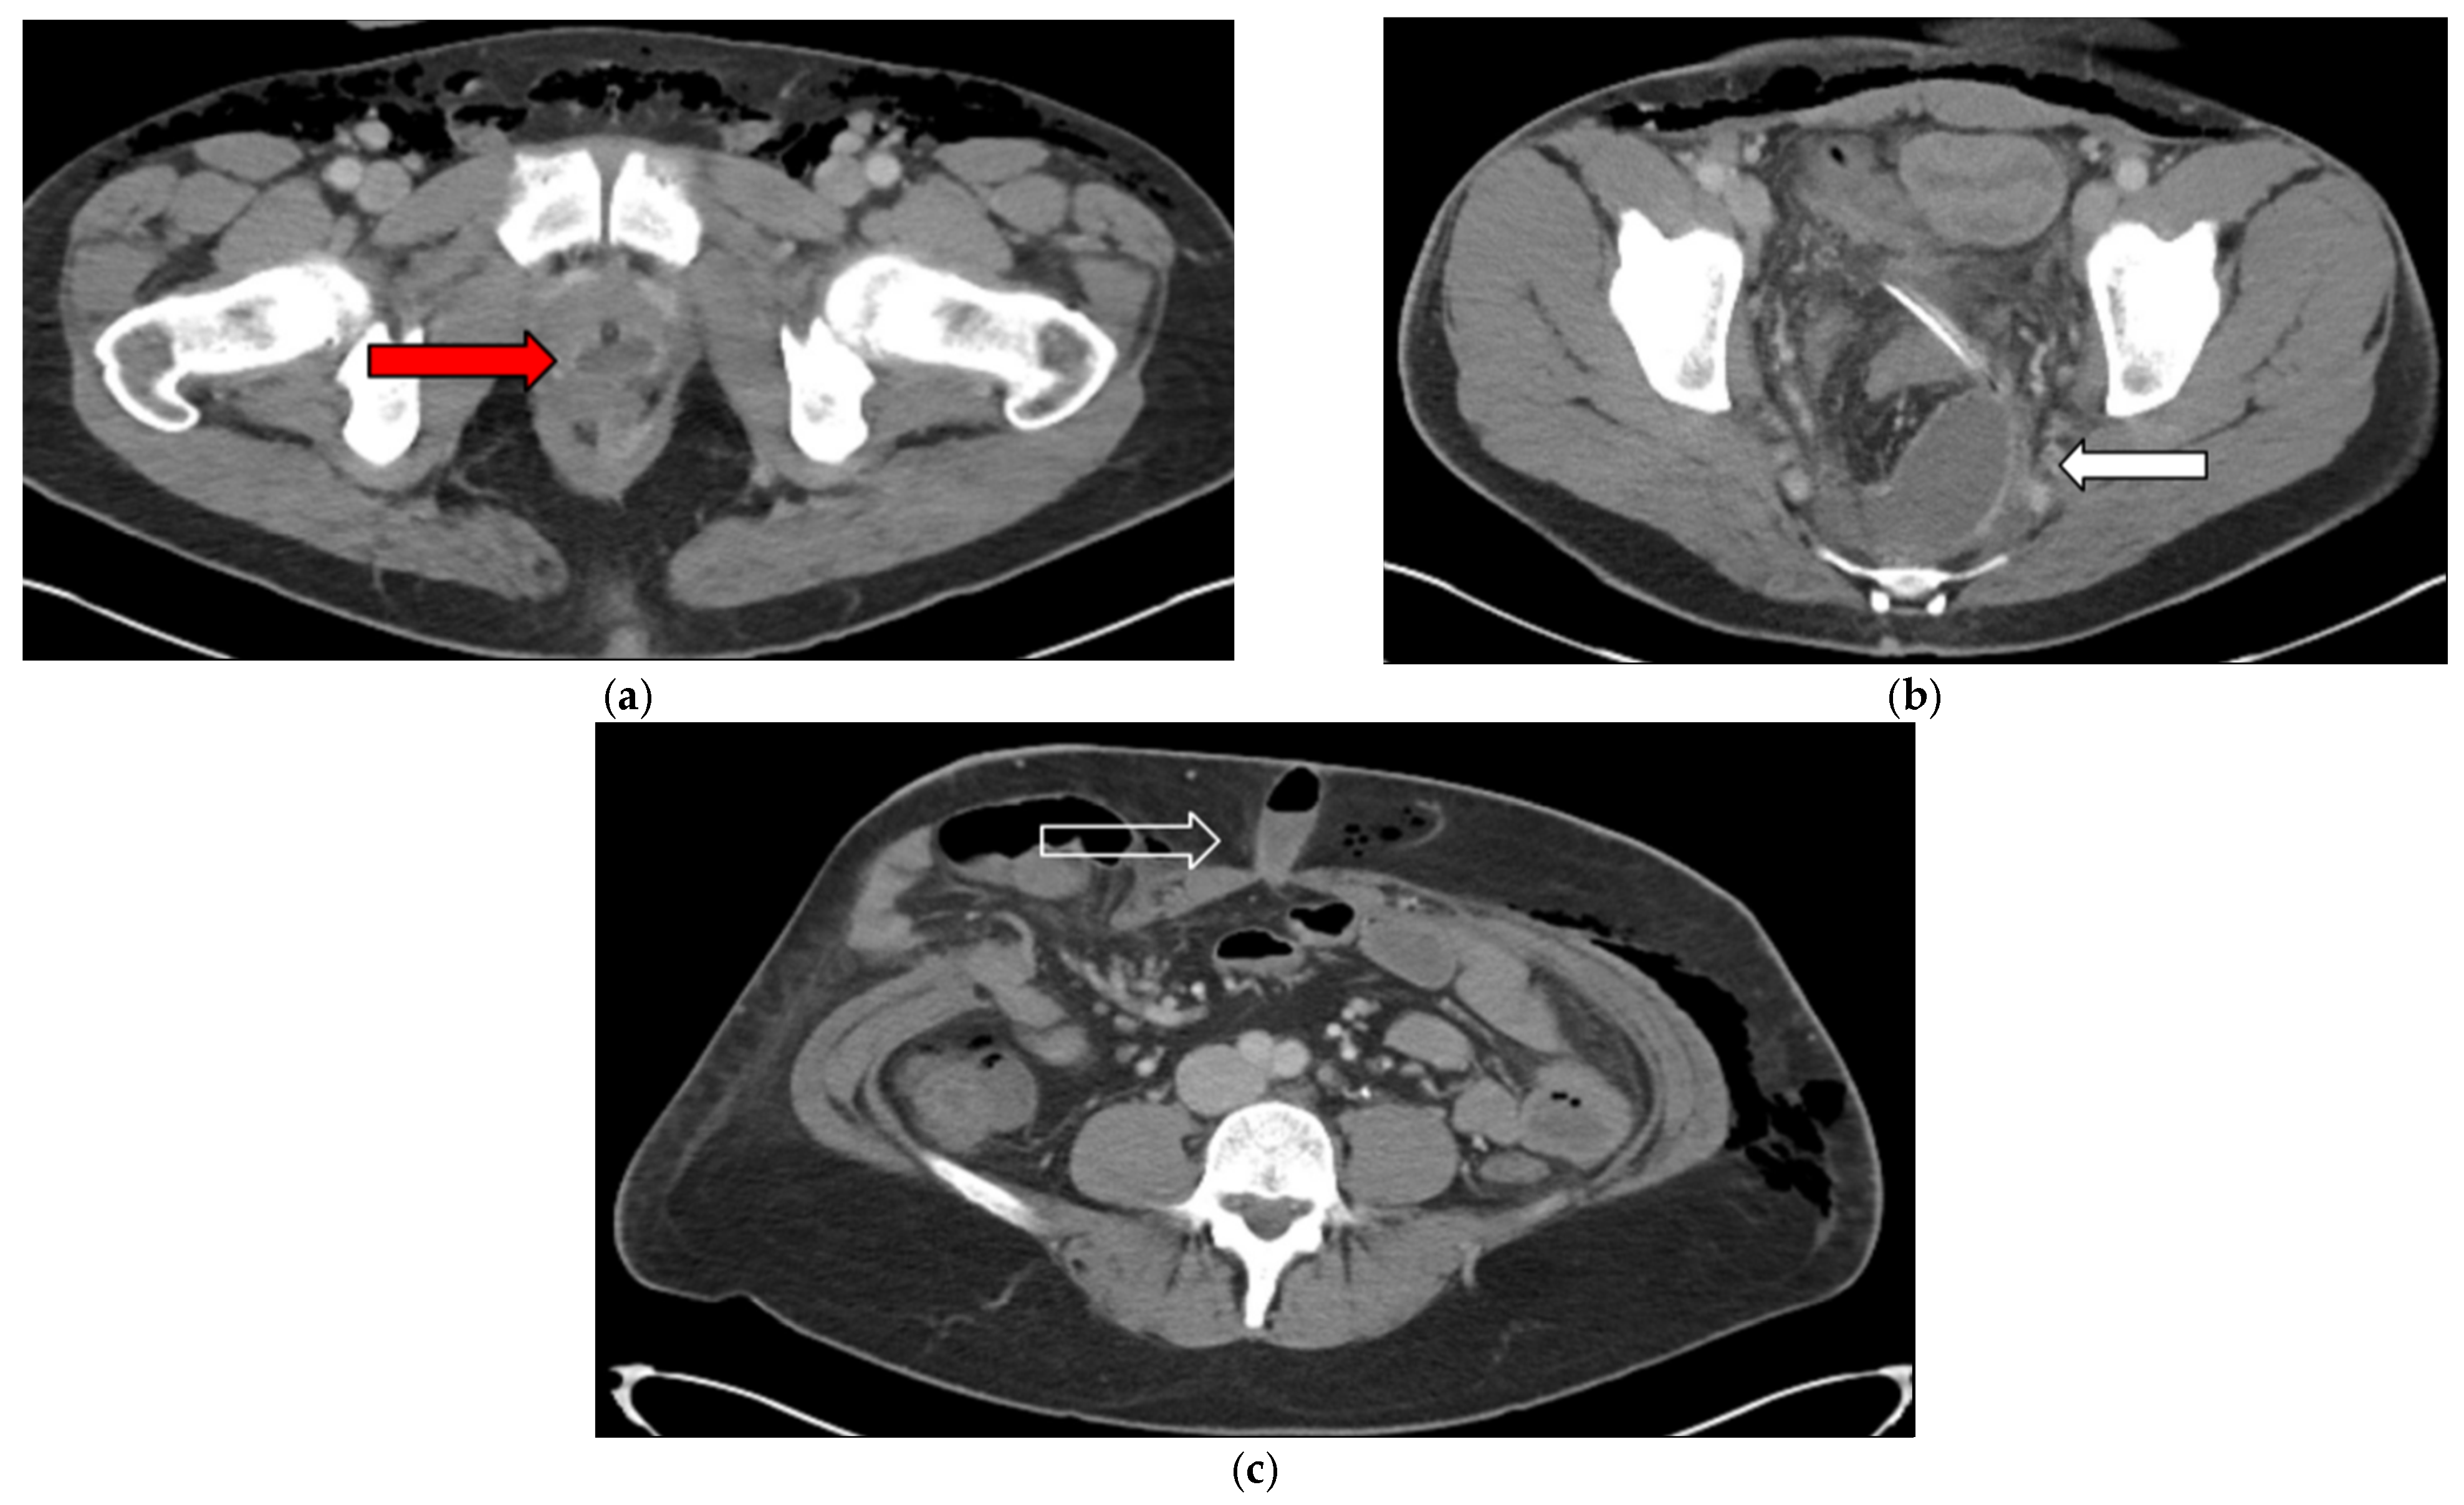

3.2. Case 2